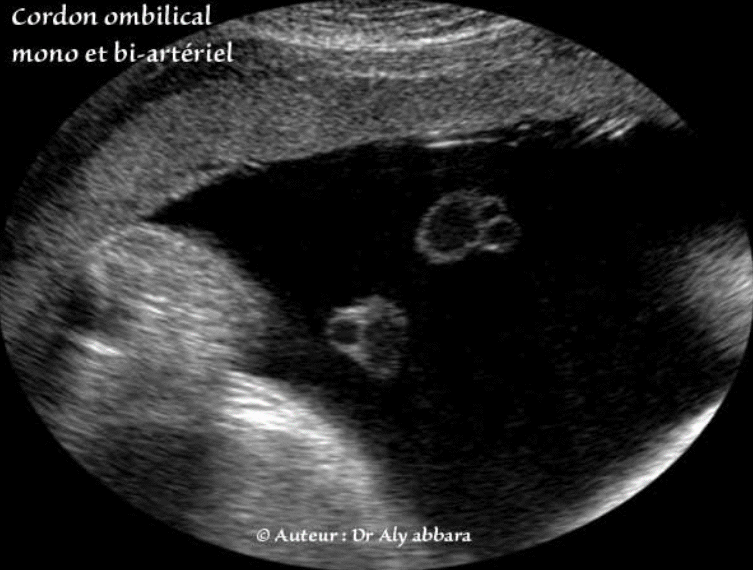

Cordon ombilical mono-artériel et bi-artériel

Cordon ombilical à artère unique et ayant une composante pré placentaire bi-artéielle

(Grossesse de 36 SA).

• Série d'images échographiques montrant un cordon ombilical mono-artériel, mais la particularité de ce cordon, c'est qu'à environ 8 cm avant sa jonction avec le placenta, son artère unique se divise en deux d'où cette disparité échographique, car sur certaines coupes, il est mono-artériel, et sur d'autres il est bi-artériel.